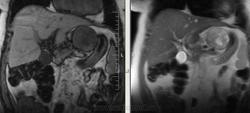

Интересные брюшные полости пошли в последнее время. Женщина, 1941 г.р. Оформлялась на операцию (по глазам), прошла УЗИ, после чего направили к нам. Жалобы только на глаза и суставы, на брюшную полость никаких. 2 года назад делала ФГС - все в порядке было. Коллеги, подскажите, пожалуйста, откуда растет эта штука? Из брюшины? Или из желудка? Или еще откуда-то?

Как-то очень близко к желудку прилежит, даже местами четко граница не прослеживается.

Согласен с Алексеем Станиславовичем. Опухоль связана со стенкой желуда, что видно на сканах 76, 77, 110, 111, стенка желудка истончена, накапливает контраст. На лейомиому в чистом виде опухоль не очень похожа, как я её себе представляю, зоны деструкции, кровоизлияния, может быть малигнизированная если. Но выглядит довольно доброкачественно в плане операбильности, имеет капсулу (не в месте контакта с желудком). Мне недавно попадалась опухоль точно такой же локализации, но имела совершенно другую структуру, прилежала к брюшине без явных признаков прорастания её. Пациентка врач, я думаю узнаю гистологию у неё, но та выглядела злокачественной.

лейомиома,лейомиосаркома ,гисо,шваннома